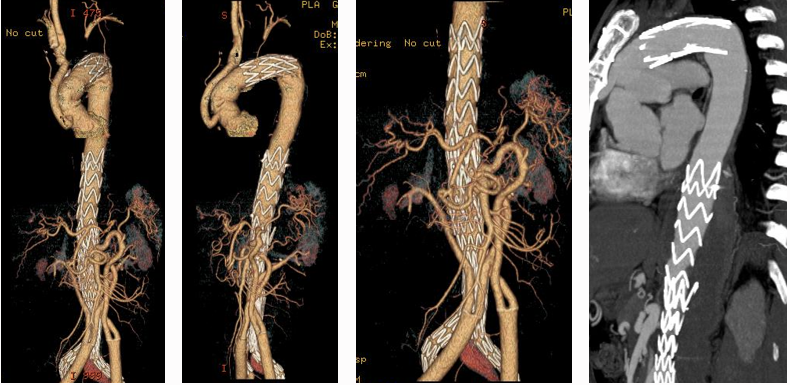

主动脉重塑差异与301分型

★ 301分型核心价值

分型依据:基于真/假腔与胸椎的空间关系(B1: 真腔贴椎体;B2: 螺旋混合;B3: 假腔贴椎体)

预后关联:

① B3型24个月胸主动脉扩张风险最高(42%,HR=13.91 vs B1型参照)

② B1型预后最佳(97%免于扩张)

意义:为TEVAR术后风险分层提供新工具(Mayo Clin Proc. 2020)